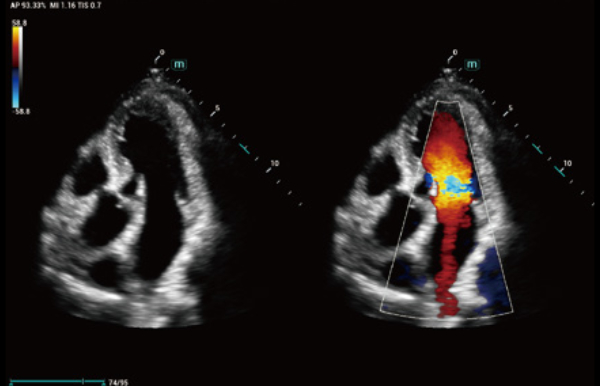

Ongeacht of u werkzaam bent in een ziekenhuis of kliniek, of uw vaardigheden aanscherpt op het gebied van algemene beeldvormingstoepassingen, vrouwengeneeskunde of cardiovasculaire specialismen, in deze serie vindt u zeer krachtige hulpmiddelen waarmee u aan kop kunt blijven.

Uitgebreide?oplossingen voor beeldvorming aangestuurd door ZST?+

Het ZST+?platform is een buitengewone innovatie en revolutie in de wereld van echografie. Het transformeert echografiegegevens van conventionele bundelvorming naar kanaalgegevensverwerking. Het overwint de traditionele afweging tussen ruimtelijke resolutie, temporele resolutie en weefseluniformiteit, en levert een uitzonderlijke beeldkwaliteit voor oneindige beeldvormingsoplossingen met non-stop verbeteringen.